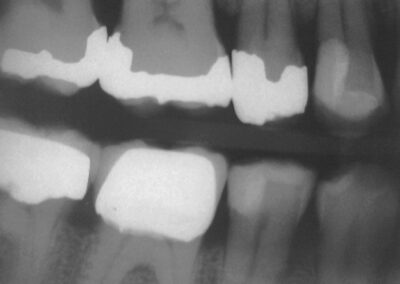

Diese Versorgung stammt aus Anfang 1985, ist also zum Zeitpunkt der Untersuchung mehr als 17 Jahre alt. Wir haben, wie man sieht, schon recht früh damit angefangen, zunächst die kleineren Defekte an Prämolaren mit Kunststoff in Säure-Ätz-Technik zu versorgen. Zu beachten ist, dass es damals ja noch keinerlei Haftvermittler gab.

Wie man sieht, besteht keinerlei klinische Indikation, die Füllungen zu erneuern. Auffällig ist, dass die Amalgamfüllungen trotz der deutlichen Gebrauchsspuren in diesem individuellen Fall immer noch relativ frisch poliert wirken, obwohl sie zu keinem Zeitpunkt nachgearbeitet wurden. Wie lange Füllungen halten, hängt eben nicht allein von der Technik und den verwendeten Materialien ab, sondern eben auch in hohem Maße von den individuellen Vorraussetzungen, die ein Patient mit bringt.